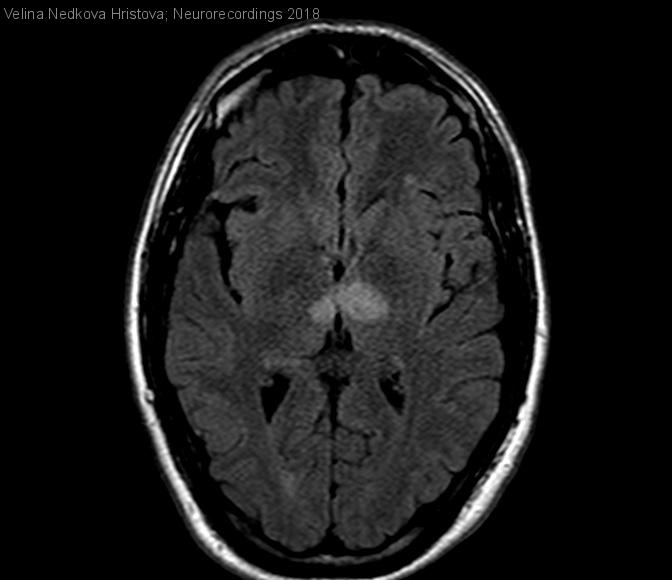

ICTUS ISQUÉMICO EN EL TERRITORIO DE LA ARTERIA DE PERCHERÓN: HALLAZGOS RADIOLÓGICOS

ICTUS ISQUÉMICO EN EL TERRITORIO DE LA ARTERIA DE PERCHERÓN: HALLAZGOS RADIOLÓGICOS

Hombre | 37 años

Diagnóstico final: Ictus isquémico agudo en el territorio de la arteria de Percherón.

Neurología: Patología cerebrovascular

Etiología: Ictus

Varón de 37 años sin antecedentes relevantes que es traído al Servicio de Urgencias por cuadro de somnolencia de unas 24 horas de evolución. En la evaluación inicial, el paciente presenta somnolencia y un nivel de...